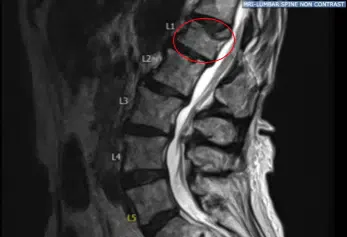

Un paciente extremadamente agradable con antecedentes médicos de osteoporosis, presentando dolor de espalda intratable y una deformidad por compresión en cuña de la primera vértebra lumbar. El examen físico mostró sensibilidad en la región paraespinal derecha en L 5 y sensibilidad en la región paraspinal izquierda en L 5.

La resonancia preoperatoria mostró un cambio hiperintenso de la señal STIR en la vértebra L1. Tras una extensa discusión y el fallo en el manejo no quirúrgico, fueron llevados al quirófano para un procedimiento de cifoplastia L1 para controlar el dolor.

Luego se utilizó un taladro manual a través de ambas cánulas para crear trayectos para los tampones de globos Kyphon. El taladro de mano fue retirado. Los tamps de globo se insertaron e inflaron a 200 PSI bilateralmente, con cuidado para restaurar la placa final. Se observó un defecto en la placa terminal superior L1 correspondiente a la resonancia magnética preoperatoria con inflado de balón.

Estado postoperatorio de la radiografía lumbar de la columna tras la vertebroplastia de la vista sagital en L1